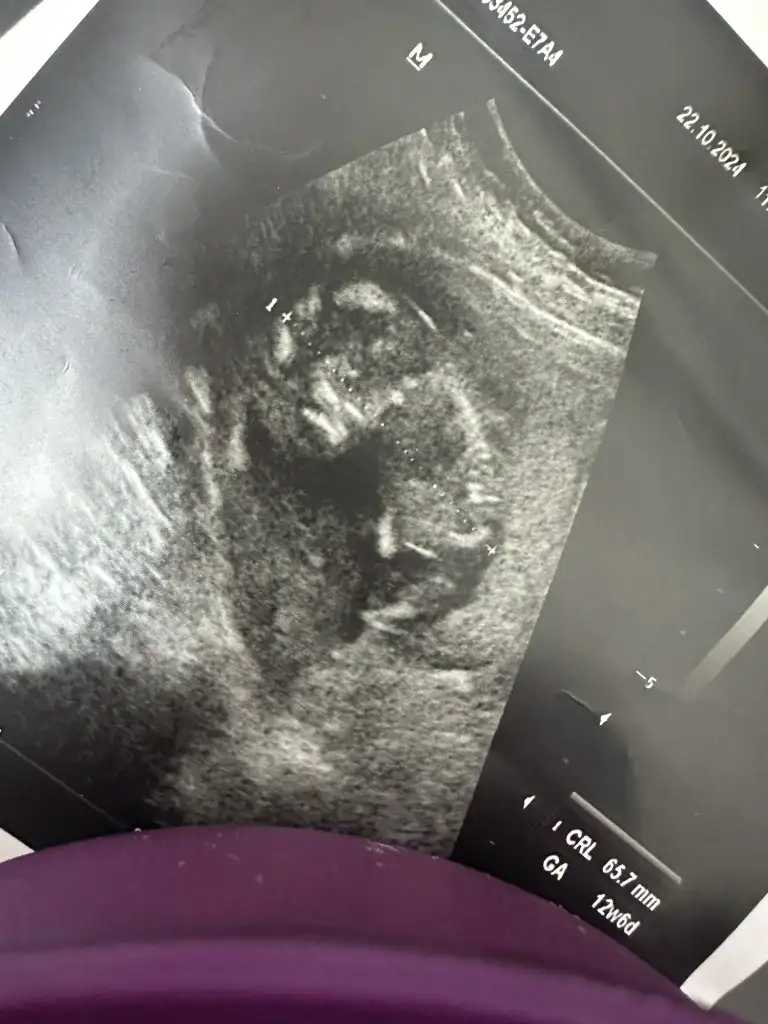

Bence erkek olacak neden bilmiyorum bende hamileyim öyle hissettim bide bana tahminde bulunur musunuz 13 haftalık olduBu da benimki teyzesi, sen bir tahminde bulunur musun

Pamuğum sanki erkek gibi geldi bana, teyzoşu onu yesin. Sağlıcakla gelsin inşallah bebişlerimiiiizBence erkek olacak neden bilmiyorum bende hamileyim öyle hissettim bide bana tahminde bulunur musunuz 13 haftalık oldu

Ya sesi çıkmıyor ultrasonun sanki kalp atışı yokmuş gibi çok kötüydü zaten ultrasonda da çok kötü görünmüyor kesesi de kendisi de bulanık görünüyor o yüzden özeller şuan en iyisiNiye korktun ki

Ya sesi çıkmıyor ultrasonun sanki kalp atışı yokmuş gibi çok kötüydü zaten ultrasonda da çok kötü görünmüyor kesesi de kendisi de bulanık görünüyor o yüzden özeller şuan en iyisAllah korusun kendini korkutma